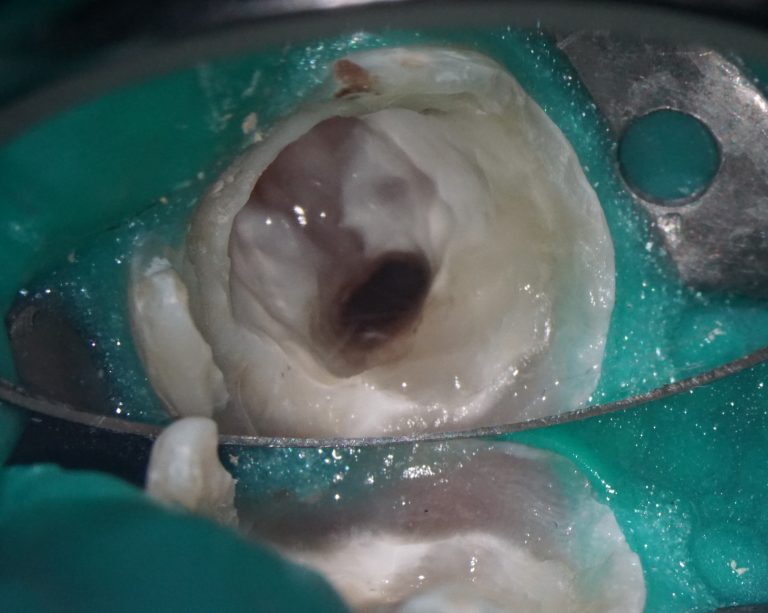

Prosthetic crown